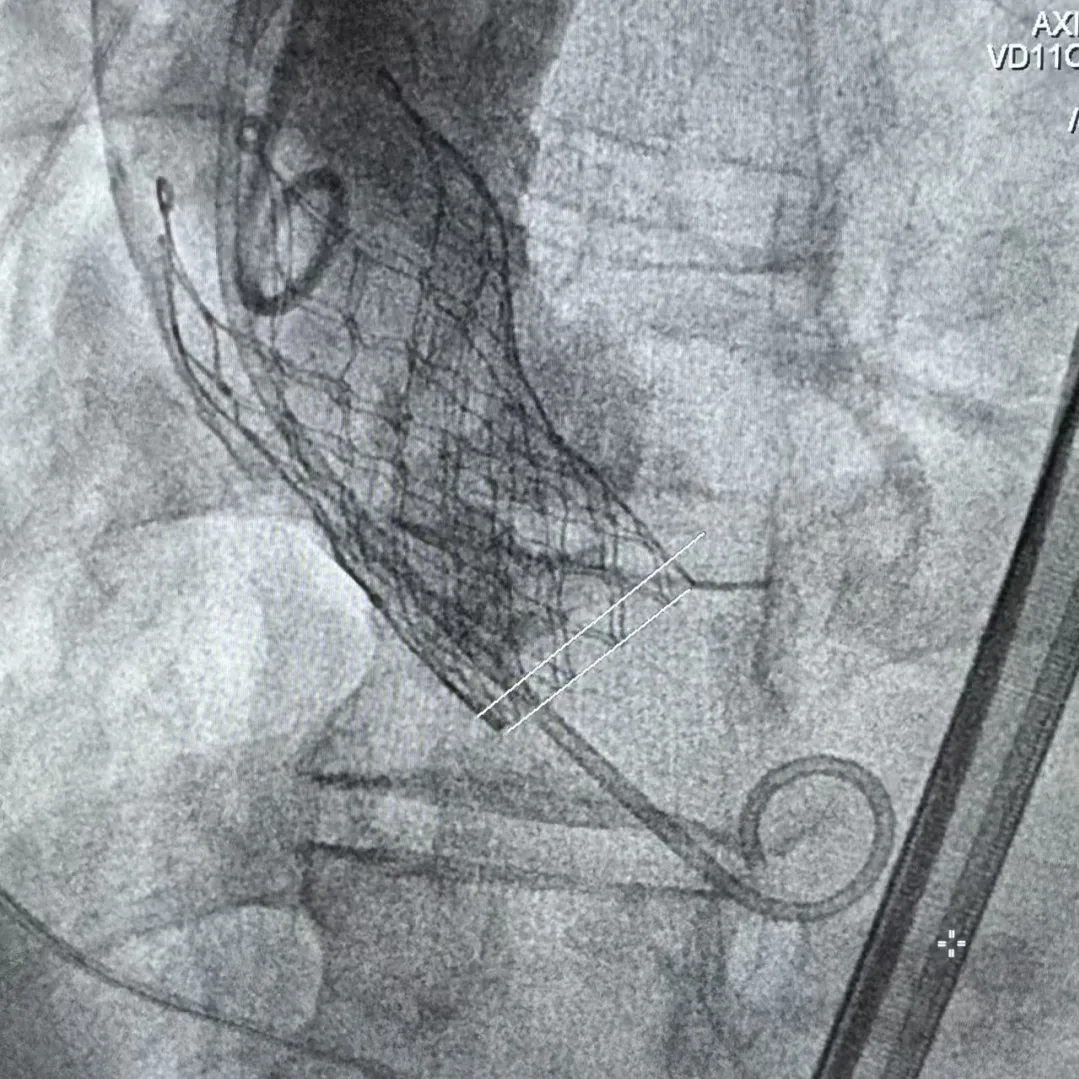

Step 1.升主动脉情况评估

Step 2.建立大鞘通路:大鞘通过升主、边进入边加弯,避免剐蹭弓部斑块

Step 3.球囊预扩:18mm球囊预扩张,无腰无漏

Step 4.输送系统进入:过弓性能优异,悬空通过,整体过程未将鞘管顶起至弓顶部

Step 5.瓣膜定位与释放:高起始位逐渐向下推送保持良好同轴性,无位移

Step 6.工作位观察:真实瓣环下方2mm,位置合适,决定释放,一次完成

Step 7.瓣膜脱钩:脱钩稳定无位移

Step 8.最终造影:真实瓣环下方3mm标准位,完全同轴,轻微反流,猪尾撤出后反流完全消失

Step 9.CuspOverlap体位验证缘对缘对齐,挂钩位于最右方,基本避开冠脉开口

过弓示意图

Step 10.验证器械同轴性,完全同轴

瓷化升主动脉和复杂弓形一直是TAVR手术中的痛点病例,既往对于这类病例一般使用可调弯的TAVR系统辅助,此次手术使用通过性良好的自展瓣+可调弯鞘,既能满足小瓣环患者的血流动力学需求,也能大幅减小患者的手术风险。该病例既能看到Prostyle A这款预装干瓣表现了良好的通过性,在瓷化血管里推进时没有明显阻力,不用过度用力,推送十分顺畅,完全悬空通过,器械释放也很稳定;也可以看到可调弯鞘对手术过程的辅助作用,实际上对术者来说我们过往的重点都放在主要的耗材本身,辅助的耗材是否搭配起来好用,对手术的帮助也非常重要,这次手术最终还有一个亮点就是瓣膜放下去同轴性非常好,几乎是和真实瓣环平齐,这也是搭配起来产生的优秀结果。

手术中其实有个关键点,在可调弯鞘过弓的时候,我们特意放慢了速度,一遍进一遍调弯,确保每一步都不触碰弓顶钙化。这台手术的成功,本质上是 “病变特点和器械特性” 的精准匹配。对同类型来说,碰到瓷化升主动脉合并复杂弓的病例,建议术前一定要把钙化范围、弓部角度这些解剖细节分析透,器械选择上不用局限于单一方案,多考虑协同作用,或许能找到更安全的路径。毕竟对我们来说,每台复杂手术的目标都一样:在保证安全的前提下,给患者带来最好的长期获益。